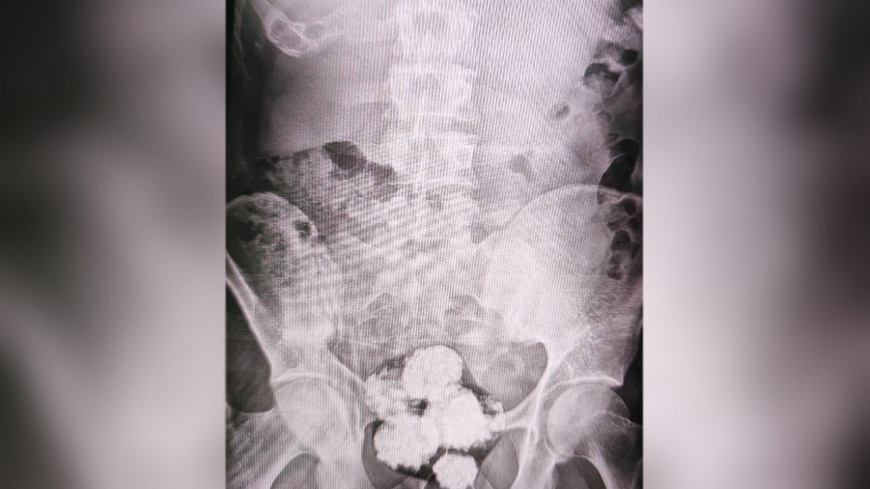

При личном досмотре мужчины заметно нервничали, однако каких-либо запрещённых веществ при них обнаружено не было. Тогда полицейскими было принято решение о проведении более тщательной проверки граждан в городской больнице, где с применением рентгеновского аппарата в желудке одного из приезжих было обнаружено пять шарообразных свёртков с неизвестным содержимым, а у второго – шесть схожих пакетиков. Экспертиза показала, что внутри свёртков находился метадон общей массой около 234 граммов.